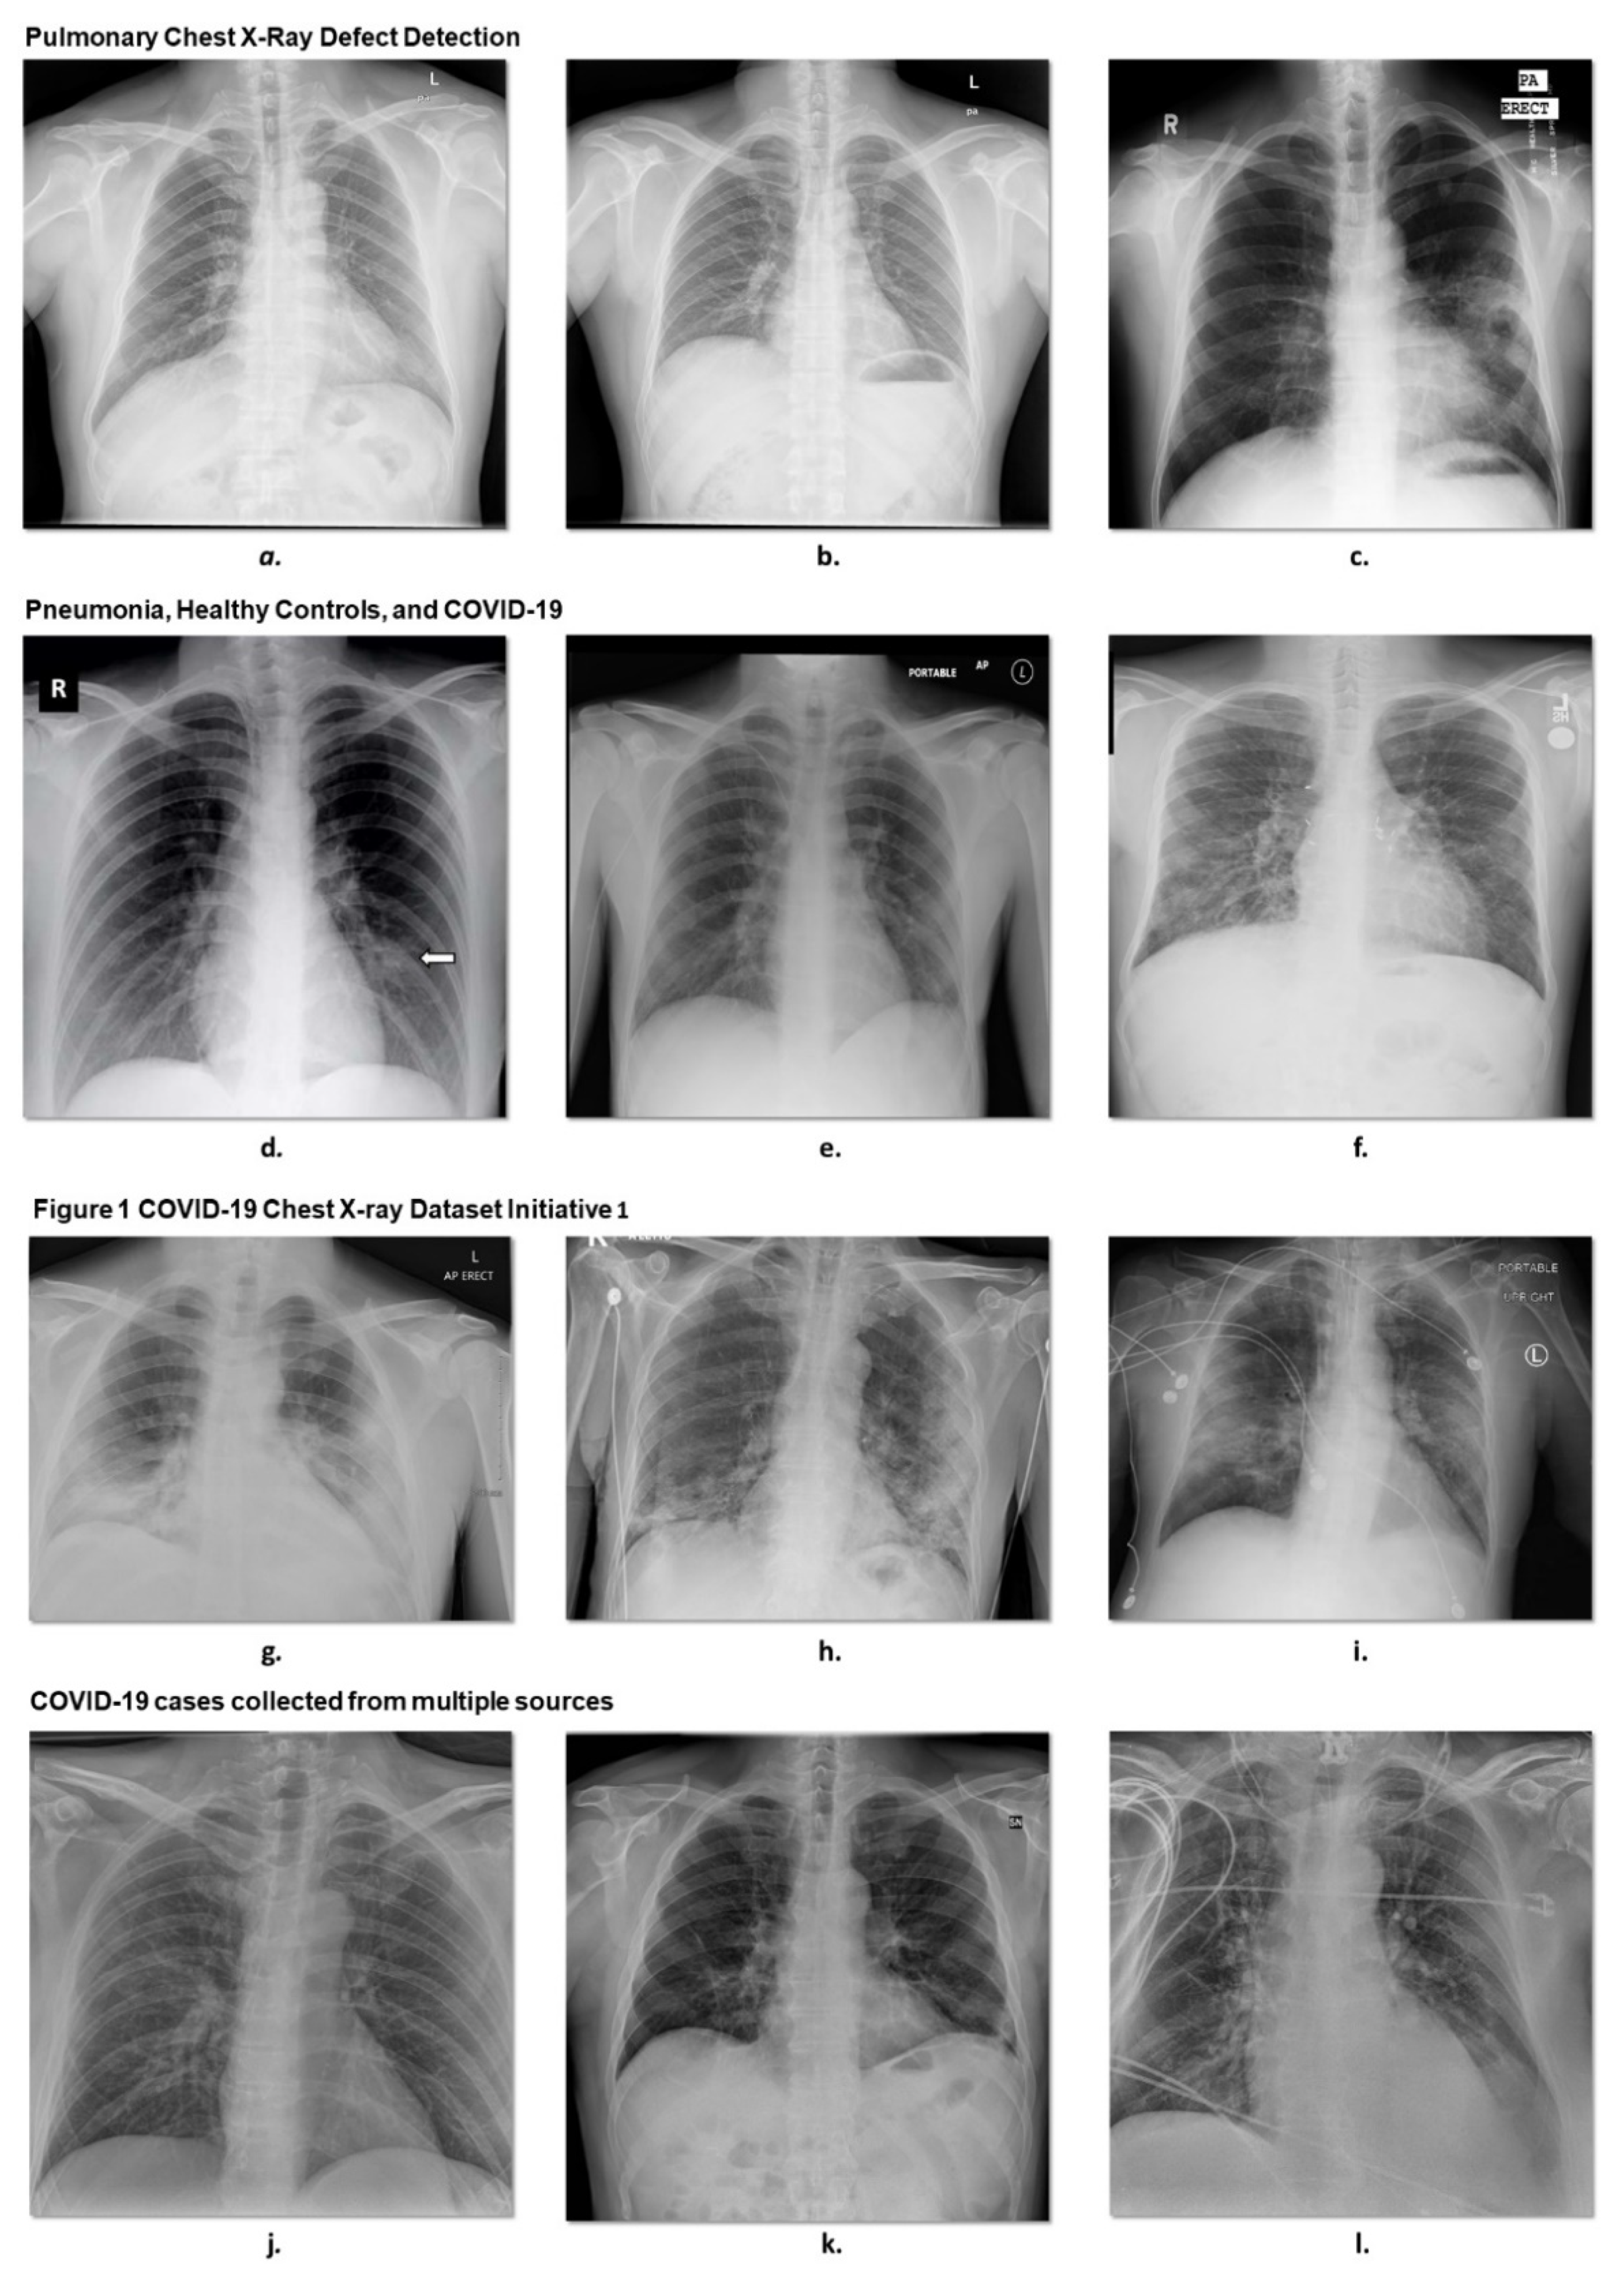

3.1.1. Pulmonary Chest X-ray Disease Detection

3.1.2. COVID-19 Cases Collected from Multiple Sources

3.1.3. Pneumonia, Healthy Controls, and COVID-19

3.1.4. Figure 1 COVID-19 Chest X-ray Dataset Initiative